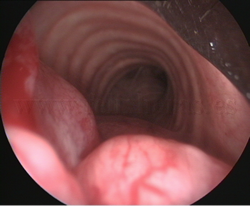

Tumores

traqueales |